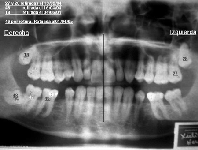

Algunos ejemplos de imágenes digitales

Pulse en las imágenes para ver la ampliación

Se agregó en rojo una medición hecha con la herramienta de medida